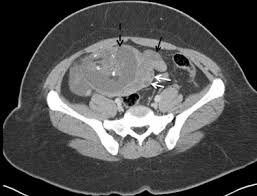

Mri anatomy of the male pelvis and pelvic floor in multiple patients aged 50 years or older. Presentation1.pptx, ct normal anatomy of the abdomen and pelvis. Anatomy ct axial abdomen and pelvis male male abdomen and pelvis ct scan form no 1. Int/ext obliques transversus spine muscles: Muscles of the pelvis that cross the lumbosacral joint to attach onto the trunk were described in. Ct and some mr imagings of nine patients who received irradiation to the pelvis and of eleven patients who received transarterial infusion for urinary bladder carcinoma were studied about the anterior and posterior attachment sites of the coccygeus muscle, the sacrouterine ligament and the lateral. Pelvic floor anatomy is complex and is being unraveled by means of magnetic resonance mr imaging. Anatomy ct axial abdomen and pelvis male from 3.bp.blogspot.com the lateral superficial muscles, the transversus and external and internal oblique muscles, originate on the rib cage and on the pelvis (iliac crest and inguinal ligament) and are attached to the anterior and posterior layers of the sheath of the rectus. Volume rendered display, ct of the pelvis • the external surface of the iliac blade is the attachment site for the gluteus medius and minimus muscles. Functional anatomy of the male pelvic floor online course: The medial thigh muscles are responsible for the adduction (movement of a body part toward the body's midline) of the leg. Schau dir angebote von ‪muscle anatomy‬ auf ebay an. Axial section through male bladder.

The labeled structures are (excluding the correct side): 48 adductor longus muscle this muscle is the most. Ct and some mr imagings of nine patients who received irradiation to the pelvis and of eleven patients who received transarterial infusion for urinary bladder carcinoma were studied about the anterior and posterior attachment sites of the coccygeus muscle, the sacrouterine ligament and the lateral. Functional anatomy of the male pelvic floor online course: Ap pelvis anatomy radiographs ct protocols pelvic ring fx ap force lateral vertical acetabular fx walls columns letournel judet view wow Weak adductor muscles may cause knee instability and adductor strain (2). They form a large sheet of skeletal muscle that is thicker in some areas than in others. Axial section through male bladder.